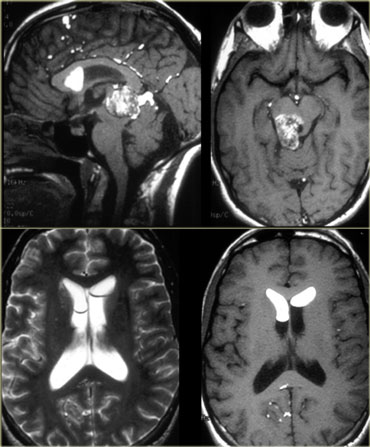

Ring enhancement

Ring enhancement is seen in metastases and high-grade gliomas.

It is also seen in non-tumorous lesions like abscesses, some MS-plaques and sometimes in an old hematomas.

On the left three different ring enhancing lesions.